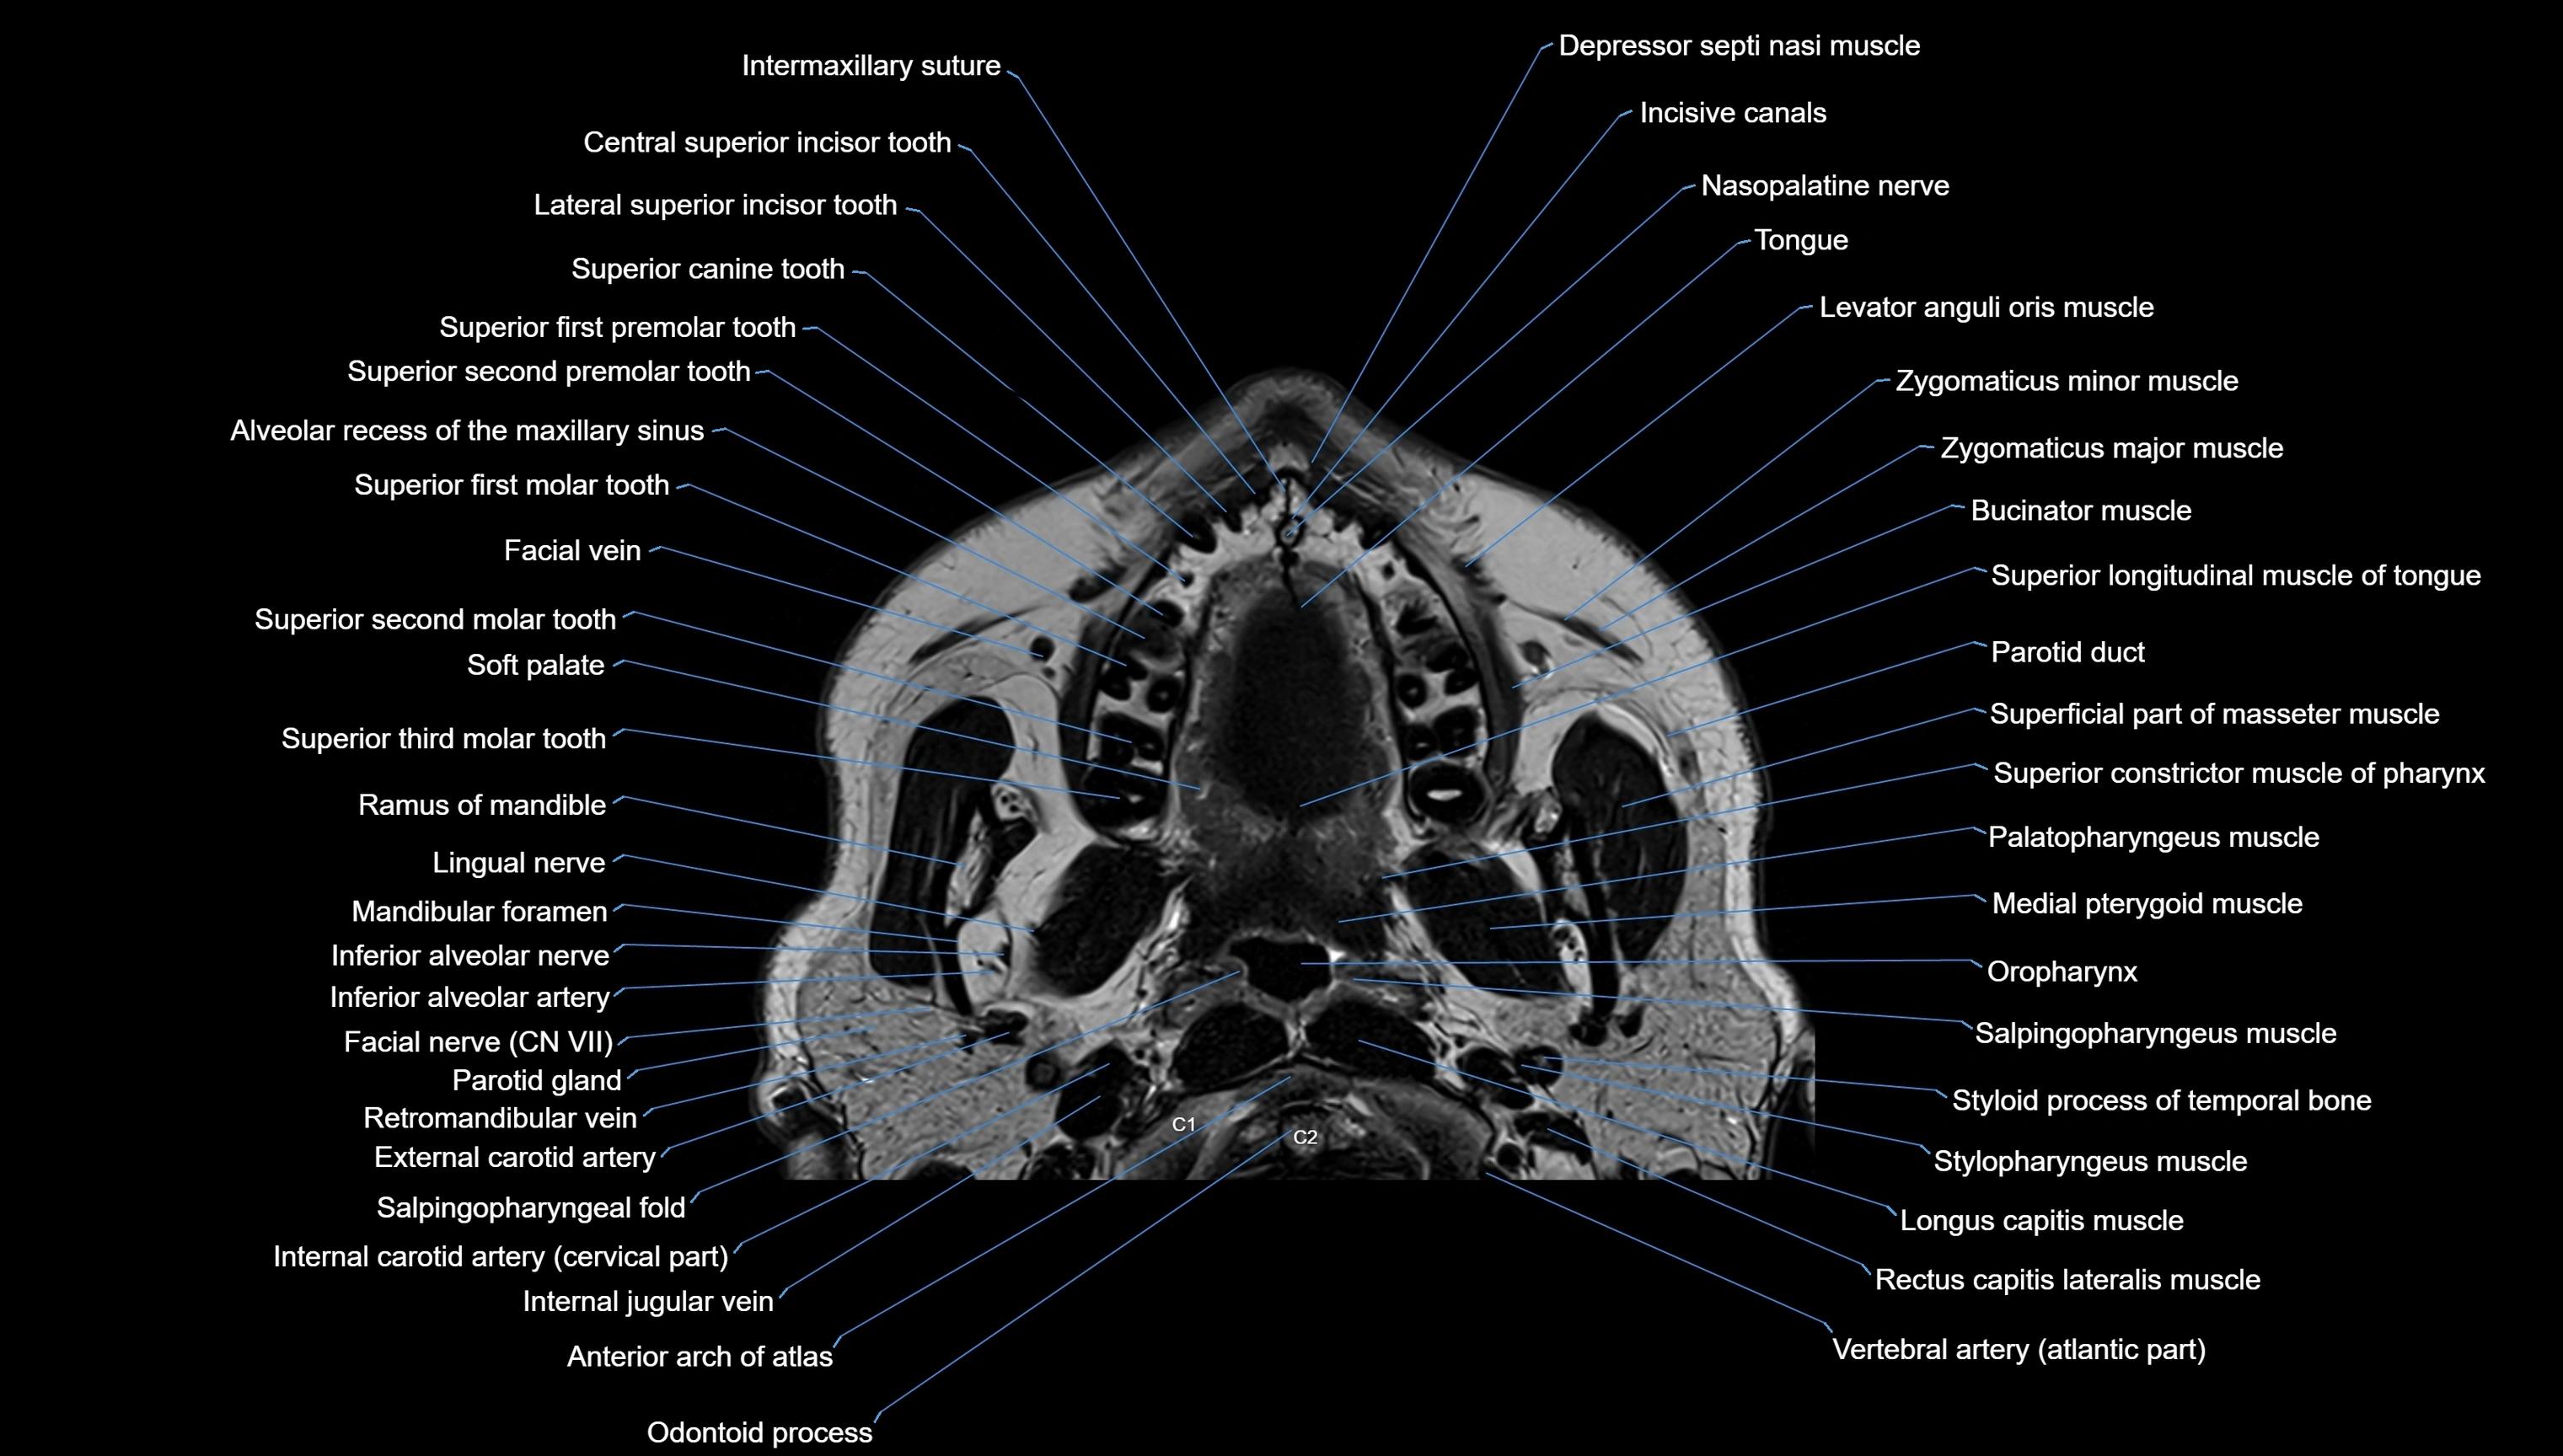

MRI images